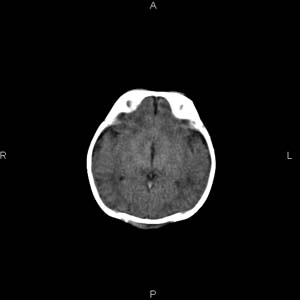

患者男,27天,出生后正常,今天中午在母亲怀里抱着吃奶在放下睡觉时发现后枕部慢慢出现一包块,来查头颅ct。无外伤史。包块内ct值47-51hu。请大家讨论。

支持脑膜脑膨出,双侧侧脑室三角区周围脑白质对称性低密度影,考虑缺血缺氧性脑病或肾上腺性脑白质营养不良。

1脑膜膨出可能性大 2产伤所致枕骨骨缝分离、头皮肿胀不除外,